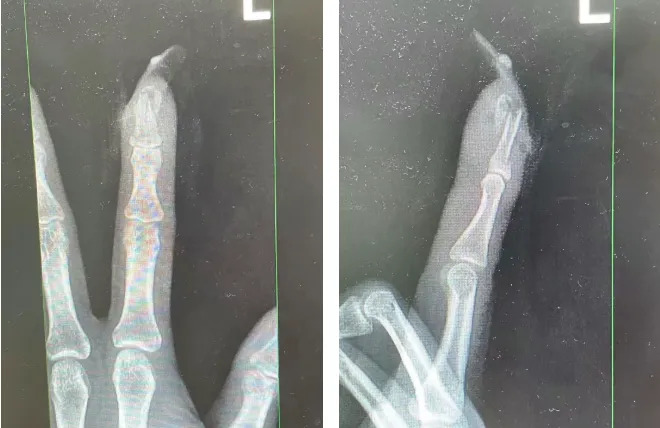

经检查

王女士指甲断裂

部分甲床外露

王女士受伤手指的X光影像。图源:杭州市临平区中西医结合医院